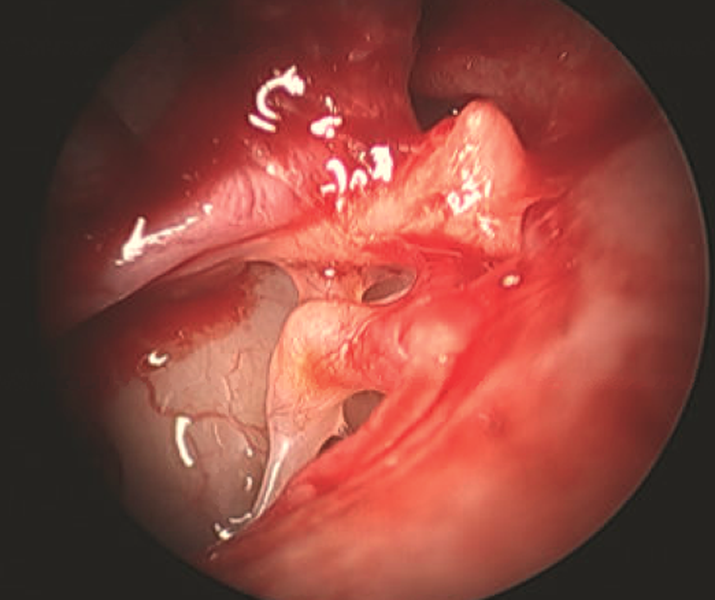

Ossicular Chain Fixation